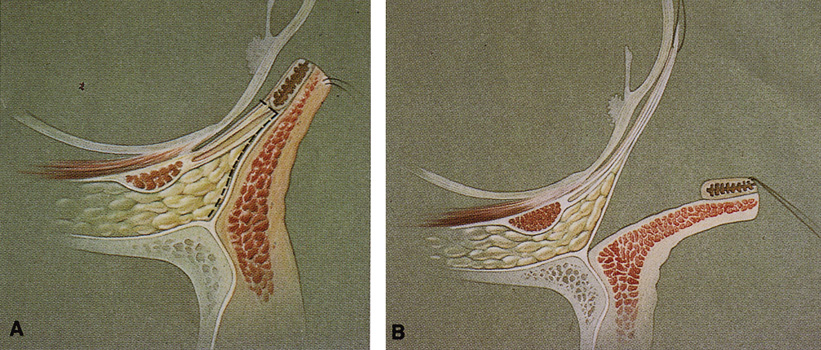

surface of the lateral rim.  Fig. 7. Coronal schematic view demonstrating major vessels penetrating periorbita

and traversing the extraperiosteal space that may be encountered during

periorbital elevation. (A, zygomaticotemporal artery; B, zygomaticofacial artery; C, communicating branch of infraorbital artery: D, supraorbital artery: E, posterior ethmoidal artery: F, anterior ethmoidal artery.) Fig. 7. Coronal schematic view demonstrating major vessels penetrating periorbita

and traversing the extraperiosteal space that may be encountered during

periorbital elevation. (A, zygomaticotemporal artery; B, zygomaticofacial artery; C, communicating branch of infraorbital artery: D, supraorbital artery: E, posterior ethmoidal artery: F, anterior ethmoidal artery.)